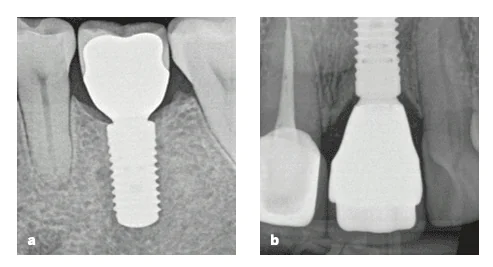

(a) A bone-level implant without platform switch. (b) A tissue-level implant. (c) A bone-level implant with platform switching.